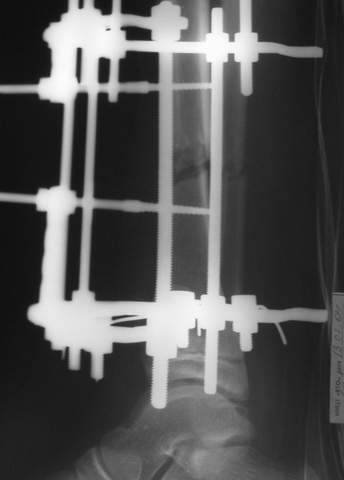

В аттачтах №№ 1 и 2 - примеры, когда 2 кольца не позволили послеоперационно

исправить смещение фрагментов большеберцовой (по ширине и вальгусное).

А казалось бы (#2) - поиграй на штангах и все влетит.

2